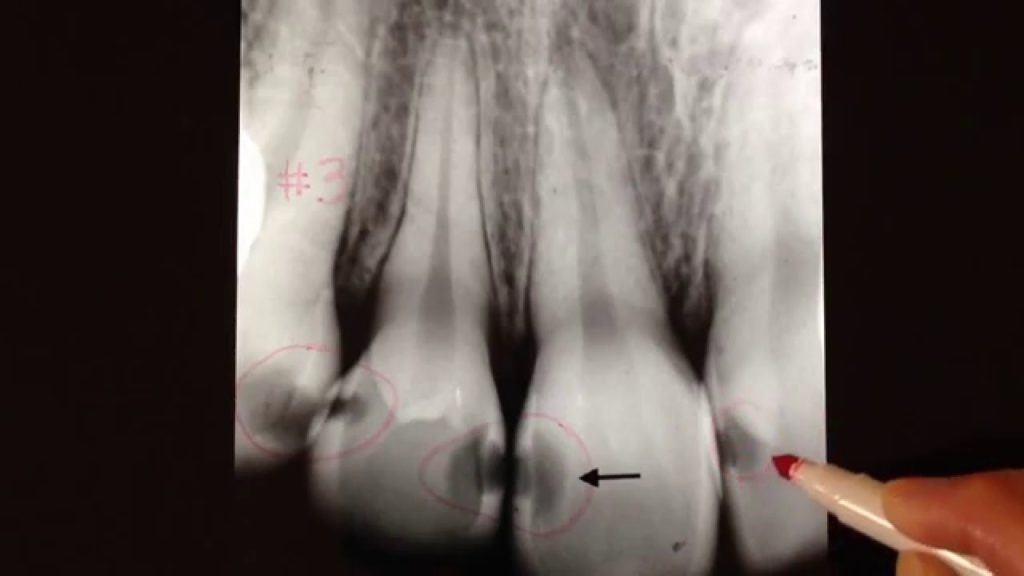

home Health Concerns Radiographic Interpretation of Dental Caries Classification (ACJ)

Radiographic Interpretation of Dental Caries Classification (ACJ)